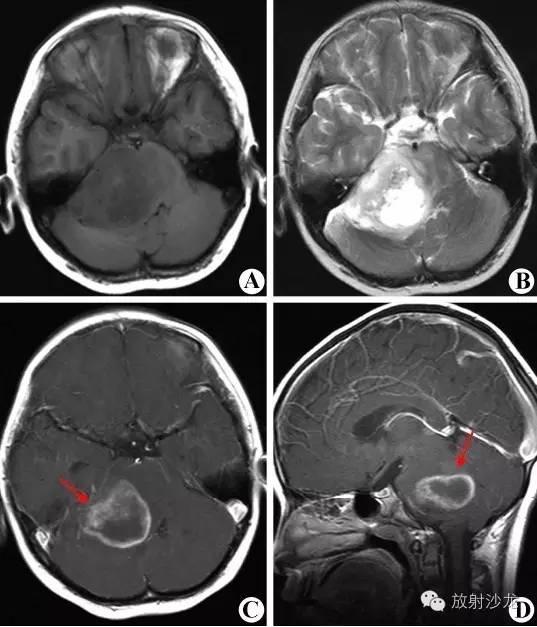

MRI平扫示双侧半卵圆区多发斑片状异常信号区,呈长T1(A)和长T2(B)改变;增强扫描(C、D)病变明显强化

5.3.2脑干肿瘤:右侧桥脑近小脑半球占位。 T1WI(A)呈不均匀等低信号,T2WI(B)呈混杂高信号;增强扫描(C、D)呈不均匀环形强化,壁厚薄不均,第四脑室受压变窄。

桥脑偏左侧占位。T1WI(A)呈不均匀低信号,T2WI(B)呈不均匀高信号。增强扫描(C、D)呈明显不均匀环形强化,第四脑室受压变形。